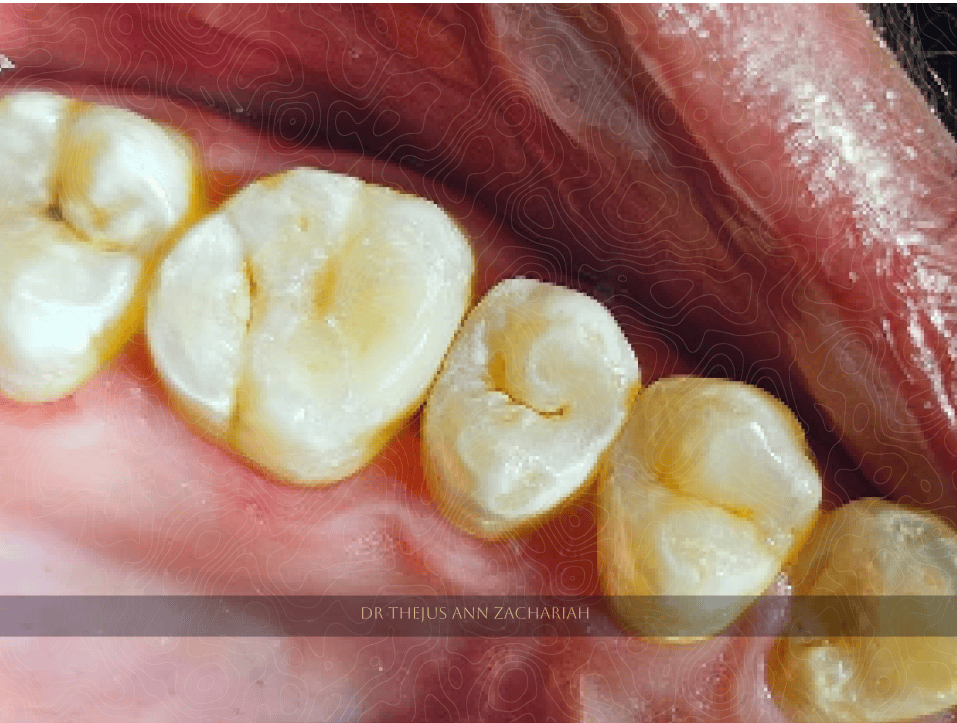

Pre-Operative

alt text